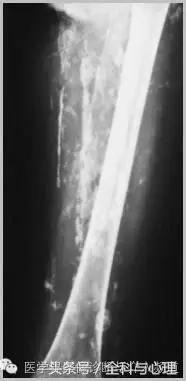

1、营养不良性钙化:由组织损伤或退变造成的钙化,没有相关的代谢障碍。

血肿机化